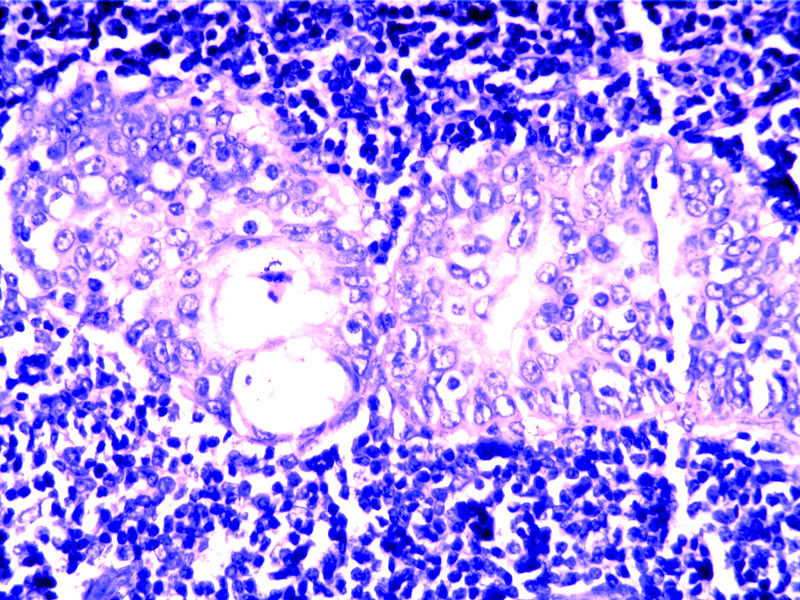

要想Hold住这个肿物的病理诊断,需要了解:

需要鉴别的肿瘤:

(1)皮脂腺淋巴腺瘤

(2)伴有淋巴组织间质的皮脂腺癌(皮脂腺淋巴腺癌)

(3)良性淋巴上皮病

(4)粘膜相关淋巴组织淋巴瘤(MALT淋巴瘤)

(5)转移性粘液表皮样癌